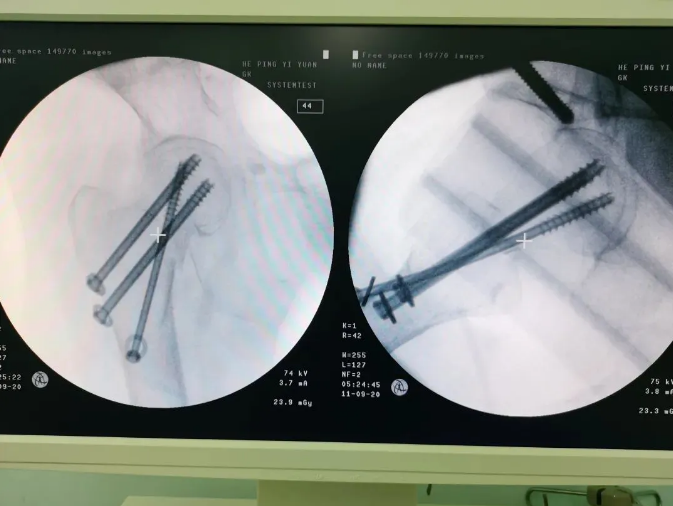

Ììçá»úеÈËÖÃÈëÂݶ¤

Âݶ¤ÖÃÈëºó

Ììçá?¹Ç¿ÆÊÖÊõ»úеÈ˵ļÓÈ룬£¬£¬£¬£¬Äܹ»ÐÖúÒ½ÉúΪÐèÒª¾ÙÐÐÊÖÊõµÄ»¼ÕßÌṩ¸üÇå¾²¡¢ÓÅÖÊ¡¢¸ßЧµÄÒ½ÁÆ·þÎñ£¬£¬£¬£¬£¬×ÊÖú»¼Õßɨ³ý²¡Ô£¬£¬£¬£¬ÊØ»¤»¼Õß¿µ½¡£¬£¬£¬£¬£¬Ìá¸ß»¼ÕßÉúÑÄÖÊÁ¿¡£¡£¡£¡£¡£¡£ÔÚÌìçá?¹Ç¿ÆÊÖÊõ»úеÈ˵ÄÐÖúÏ£¬£¬£¬£¬£¬ÊõÖл¼ÕßÇпڽöÈý¸öС¿×£¬£¬£¬£¬£¬³öѪÁ¿ÉÙ£»£»£»£»£»Êõºó³ÂÆÅÆÅ¾Ò»¶Îʱ¼äµÄ¿µ¸´ÑµÁ·±ã¿ÉÏ´²Ô˶¯£¬£¬£¬£¬£¬ÏÖÔÚÒÑ¿µ¸´³öÔº¡£¡£¡£¡£¡£¡£

Ììçá?¹Ç¿ÆÊÖÊõ»úеÈËÄܹ»¸¨Öú¿ªÕ¹¼¹ÖùÍâ¿ÆÊÖÊõÒÔ¼°´´É˹ǿÆÊÖÊõ£¬£¬£¬£¬£¬ÒÔ»úе±Û¸¨ÖúÍê³ÉÕâЩÊÖÊõÖеÄÊÖÊõÆ÷е»òÖ²ÈëÎïµÄ¶¨Î»¡£¡£¡£¡£¡£¡£ ²úÆ·¼æÈÝ2DÓë3Dģʽ£¬£¬£¬£¬£¬¶ÀÍÌÈ붤µã¼°¶¤µÀÅÌËãÖÇÄÜËã·¨£¬£¬£¬£¬£¬»úе±Û¾«×¼Ô˶¯µ½ÍýÏëλÖ㬣¬£¬£¬£¬½èÖú¹Ç¿ÆÖ¸µ¼Æ÷£¬£¬£¬£¬£¬ÎªÒ½ÉúÌṩ¾«×¼Îȹ̵ĵ¼ÕëÖÃÈë·¾¶¡£¡£¡£¡£¡£¡£Æ¾Ö¤ÊõÖÐÍýÏ룬£¬£¬£¬£¬Ò½Éú¿ÉÒÔ¾«×¼Éè¼Æ²¢ÖÃÈëÄÚÖ²ÈëÎï¡£¡£¡£¡£¡£¡£ Ììçá?Áí±Ùõè¾¶£¬£¬£¬£¬£¬Ê¹Í¨ÀýÊÖÊõ¾«×¼Î¢´´»¯¡¢ÖØ´óÊÖÊõ±ê×¼»¯¡¢Òªº¦²Ù×÷ÖÇÄÜ»¯¡¢Ò½ÁÆ×ÊÔ´¾ùµÈ»¯£¬£¬£¬£¬£¬ÁÙ´²ÓÅÊÆÏÔÖø£¬£¬£¬£¬£¬Öǻ۹ǿƵÄδÀ´¿ÉÆÚ¡£¡£¡£¡£¡£¡£